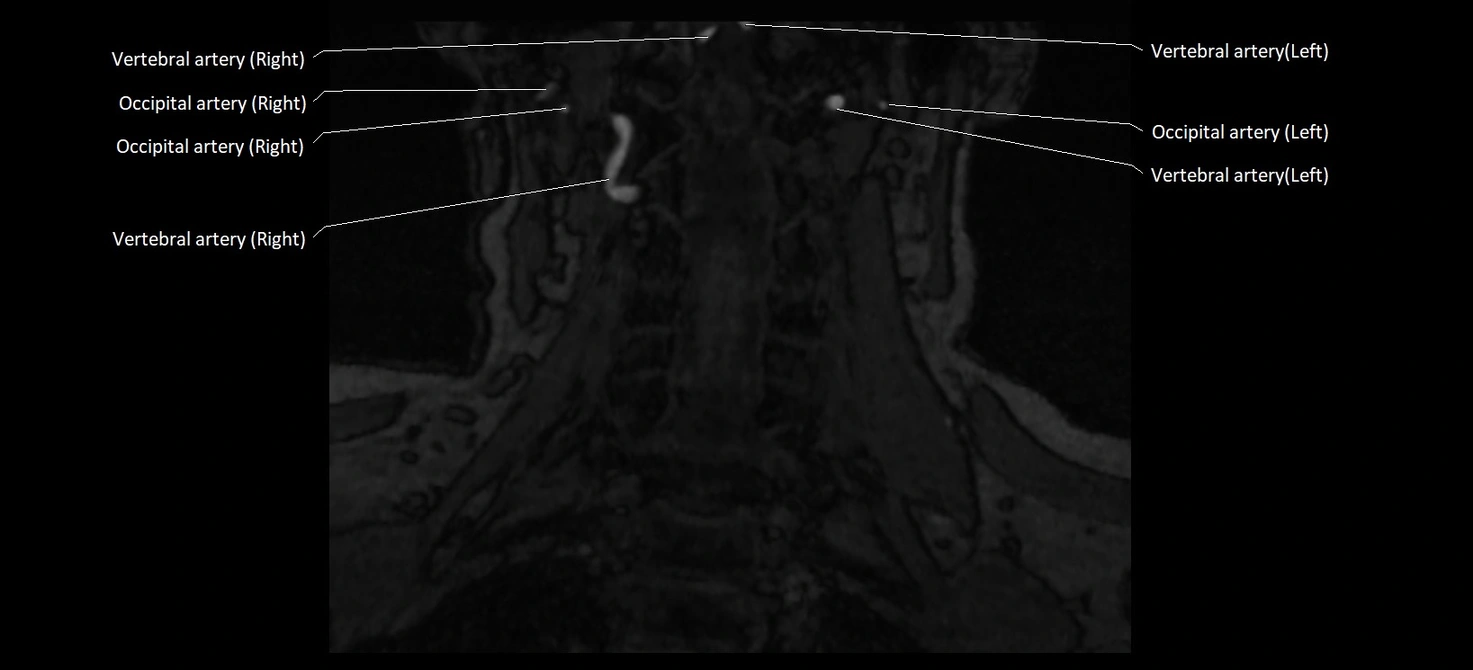

MRI images

image